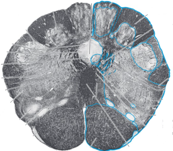

15

Q

Name this brainstem cross section:

A

Rostral Medulla